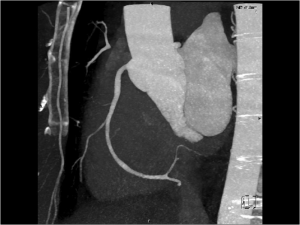

In line with our commitment to provide world-class facilities and deliver excellence in clinical care, San Radiology recently installed the cardiac-capable Siemens FORCE CT Scanner (384-slice, Dual Source). In March 2015, in a world-first, San Radiology achieved the lowest dose of radiation ever reported for Cardiac CT imaging, according to the supplier Siemens Healthcare. Our average dose for Cardiac CT is significantly lower than the safety reference guidelines used for CT in Australia (in many instances up to 98% lower).